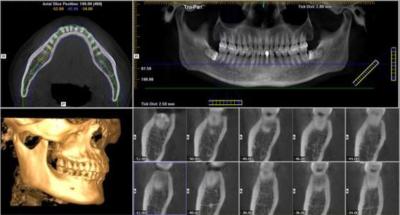

采用具有扫描快、精度高、范围大、放射剂量极低的德国卡瓦360度口腔体层摄影扫描系统cbct。通过CT诊疗,集全景、头颅侧位、CBCT功能于一体,精确定位头颅数据采集,提供高清晰度3D诊断图片,掌握治疗过程。

§ 专业软件分析

一次3D扫描即可获取全部原始记录,在制定正畸治疗计划的过程中创建全景片图像、头颅侧位片图像等所需影像及测量分析,精确确定阻生和埋伏牙的位置。

§ 可视效果评估

口腔CT测量的牙齿、牙槽骨数据可通过计算机导入到系统进行分析,精确测算出每一颗牙齿进行牙齿矫正所需的生物拉力,评估终效果。

▲利用数字化技术精准分析口内每一处细节